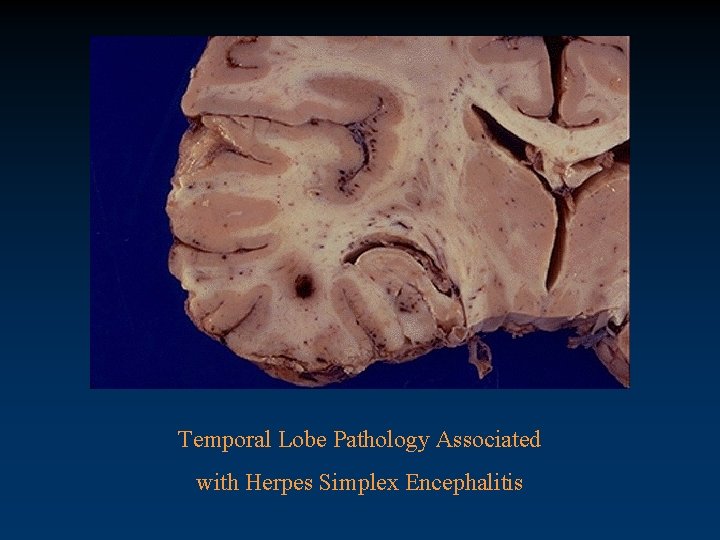

Temporal Lobe Pathology Associated with Herpes Simplex Encephalitis